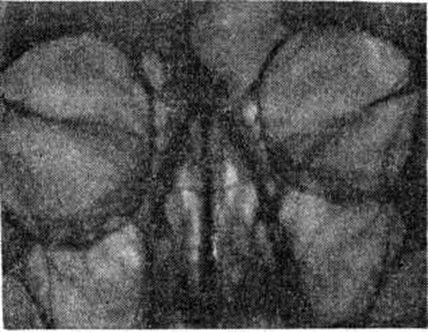

ТоксоплазмозТоксоплазмоз (toxoplasmosis) — паразитарная болезнь, вызываемая простейшими и характеризующаяся поражением нервной и лимфатической систем, глаз, скелетных мышц, миокарда и другие Различают приобретённый и врождённый Токсоплазмоз Возбудитель токсоплазмоза Toxoplasma gondii открыт в 1908 год французский исследователями Ш. Николлем и Мансо (L. Manceaux), обнаружившими его в Тунисе у грызунов Ctenodactyluo gundi, и итал. исследователем Сплендоре (A. Splendore), выявившим его в Бразилии у кроликов. На территории СССР токсоплазмы впервые были выделены от сусликов Н. А. Гайским и Д. Н. Засухиным в 1930 год В 1923 год чешский исследователь Янку (3. Jankii) обнаружил токсоплазмы в глазу умершего ребенка, доказав тем самым восприимчивость людей к заражению этим паразитом. Первый случай врождённого Токсоплазмоз человека описали Вольф (A. Wolf), Кауэн (D. Cowen) и Пейдж (P. Paige) в 1939 год Важной вехой в изучении Токсоплазмоз была разработка методов его иммунодиагностики. Оригинальную серологическую реакцию с красителем предложили в 1948 год Сейбин (А. В. Sabin) и Фельдман (Н. A. Feldman) — реакция Сейбина — Фельдмана (РСФ). Кожную пробу с токсоплазмином предложил в том же году Френкель (J. К. Frenkel). В 1953 год Айлс (D. Eyles) и Коулмен (N. Coleman) ввели в практику лечения Токсоплазмоз дараприм (хлоридин) в комбинации с сульфаниламидами. Систематическое положение Toxoplasma gondii оставалось неопределенным до открытия Хатчисоном (W. М. Hutchison) в 1969 год половой фазы развития паразита, которая протекает в кишечнике представителей семейства кошачьих. Этиология. Возбудитель Токсоплазмоз— облигатный внутриклеточный паразит Toxoplasma gondii, отряда Eucoccidiida, типа Apicomplexa, относится к тканевым цистообразующим кокцидиям. Наименование рода Toxoplasma (греческий toxon лук, арка, дуга + plasma вылепленное, оформленное) определяется формой паразита (в виде полумесяца). Развитие токсоплазм происходит со сменой хозяев. Окончательные хозяева токсоплазм — кошка и некоторые другие представители кошачьих, промежуточные — млекопитающие (кроме кошачьих), дикие животные (свиньи, овцы и другие), человек и птицы. В процессе развития токсоплазм установлены следующие фазы: внекишечная тканевая фаза — бесполое размножение токсоплазм (эндодиогения и эндополигения) в различных тканях промежуточных хозяев; кишечная фаза — бесполое размножение (шизогония) и половое размножение (гаметогония) токсоплазм в клетках эпителия слизистой оболочки кишечника окончательных хозяев; фаза спорогонии, которая начинается в просвете кишечника окончательных хозяев и заканчивается в окружающей среде (рисунок 1). Промежуточные хозяева, в том числе и человек, могут заражаться либо спорозоитами из спорулированных ооцист, попавших в почву с фекалиями кошек (или с рук, пола, мебели, предметов обихода, загрязнённых фекалиями кошек), либо цистозоитами из цист, содержащимися в тканях других промежуточных хозяев (в частности, при употреблении людьми в пищу недостаточно термически обработанного мяса); либо эндозоитами, также содержащимися в тканях промежуточных хозяев (проникновение через поврежденную кожу при обработке тушек инвазированных животных). В организме человека (промежуточного хозяина), спорозоиты, эндозоиты и цистозоиты активно проникают в клетки (рисунок 1, I, а, б; рисунок 2) различных тканей и органов, где проходит бесполое развитие. Оно заключается в размножении их путём эндодиогении — внутреннего почкования (рисунок 1, I, в), в результате чего образуются две дочерние клетки (рисунок 1, I в, 6 рисунок 3), и эндополигении, при которой образуется четыре и более дочерних особей (рисунок 1, I в, 7). Ритм размножения эндозоитов определяется продолжительностью развития одного поколения токсоплазм и может быть быстрым (3—5 час) при остром течении Токсоплазмоз либо замедленным (10—15 часов и более) при хроническом Токсоплазмоз При остром течении инвазии в результате повторных делений эндозоитов образуются псевдоцисты (рисунок 1, I г, 8) — скопления эндозоитов одной генерации, окружённые оболочкой паразитофорной вакуоли, сформированной клеткой хозяина. Поражённая клетка, переполненная эндозоитами разрушается (рисунок 1, I д), эндозоиты активно внедряются в соседние клетки, где вновь начинается бесполое развитие (рисунок 1, I а—д). При хроническом Токсоплазмоз медленный темп размножения эндозоитов (рисунок 1, I е) приводит к образованию цистозоитов (рисунок 1, I ж), находящихся внутри цист и продолжающих медленно размножаться (рисунок 1, I з). |

Рис. 2. | ||